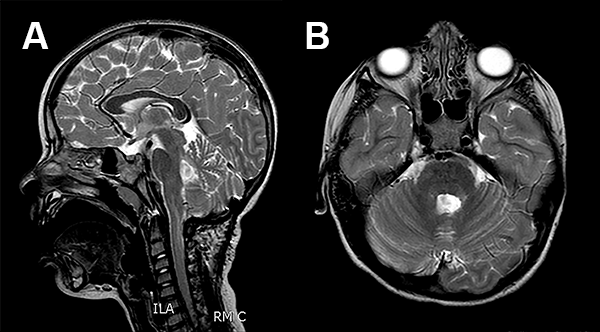

La RMN de encéfalo evidenció una lesión expansiva cerebelosa en contacto con el IV ventrículo y los pedúnculos cerebelosos superior y medio izquierdo, con leve efecto de masa que no realza con contraste (fig. 1).

Figura 1: Caso 1 imágenes prequirúrgicas.